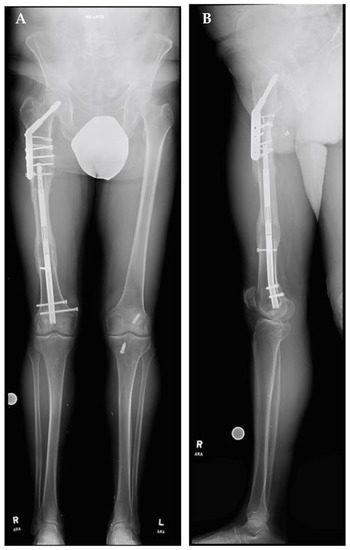

A right femoral osteoplasty was performed and a Precice MILN was inserted using the methods described above (Figure 2). The patient began lengthening as instructed on postoperative day five. He attended physical therapy and took vitamin D and calcium supplementation, as well as oxycodone as needed for pain management. Initial ROM of the knee joint was restricted from 0–50°, but full range was regained two months after surgery. He finished distraction 46 days after surgery (Figure 3). The patient completed consolidation 152 days after surgery and experienced no complications. At his latest follow-up appointment, his long leg films (Figure 4) demonstrated complete healing, remodeling, and equal limb length. The patient has returned to his active lifestyle, including skiing, and reported that he felt better on his bike and skis.

Figure 4.

Post-traumatic femoral lengthening in a 71-year-old male patient at his final follow-up appointment. (A) Anteroposterior bilateral long leg and (B) lateral right long leg after consolidation of regenerate, with Precice MILN in place. Gray dots on the bottom represent X-ray calibration spheres.